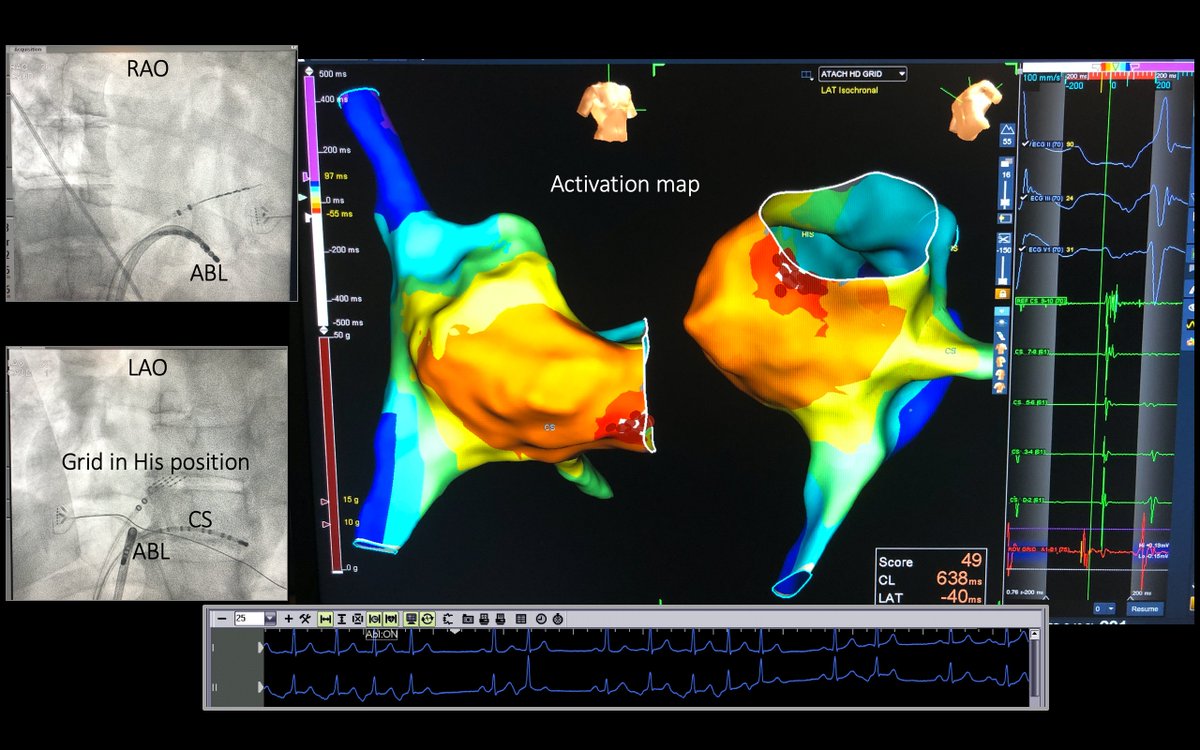

Micro-reentrant AT Mondays?!? Let's go! 🎯 Entire re-entrant circuit on the Grid EGMs imperceptible on recording system <0.06 mV Annotated automatically based on frequency w #OTNF One burn term 🔥🔥#MapMoreBurnLess @AbbottCardio

Entire re-entrant circuit on the Grid

EGMs imperceptible on recording system &amp;lt;0.06 mV

Annotated automatically based on frequency w #OTNF

One burn term 🔥🔥#MapMoreBurnLess